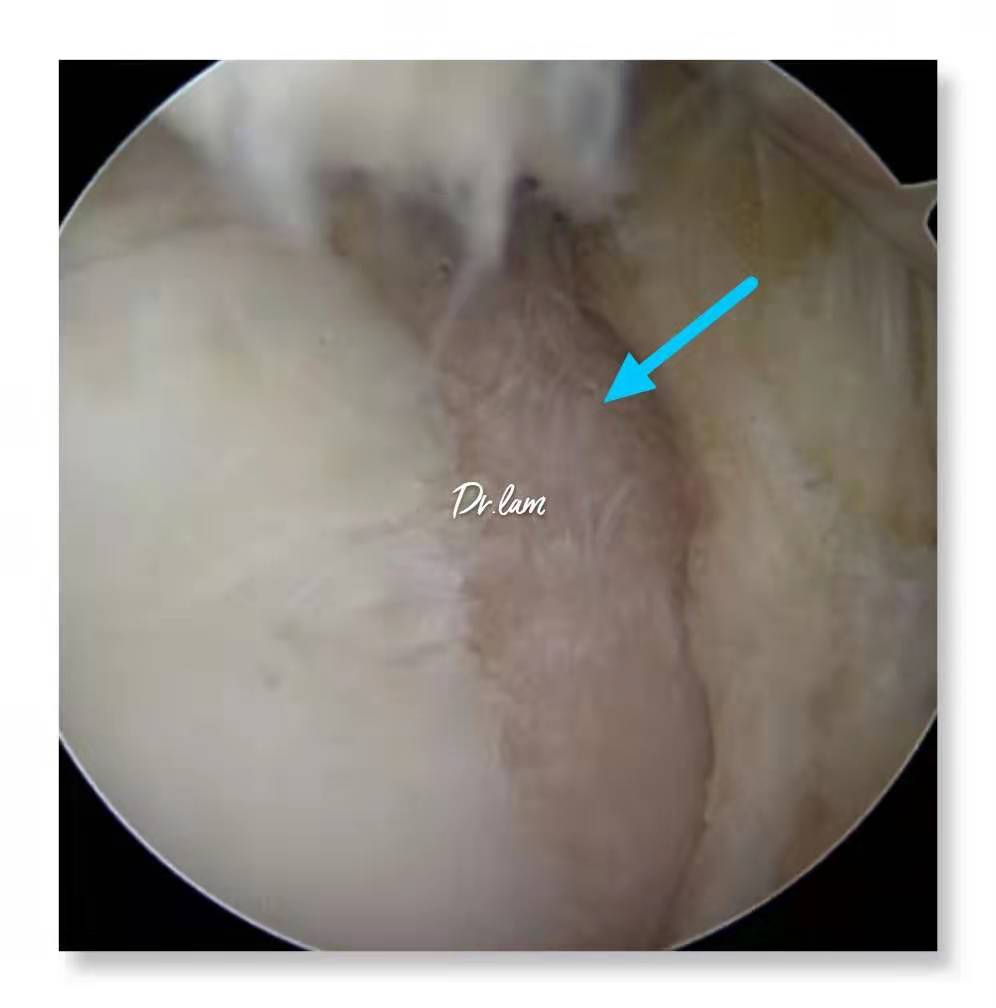

最后,我们再一起看看几张图片,加深了解这个容易被忽视的疾病。

关节镜下滑膜皱襞综合征导致轻度的髌骨软骨软化

关节镜下病变的滑膜皱襞严重磨损股骨内侧髁软骨

严重病变的滑膜皱襞变成像粗绳那样卡在关节软骨面之间,时间久很容易损伤软骨面导致严重关节病损。